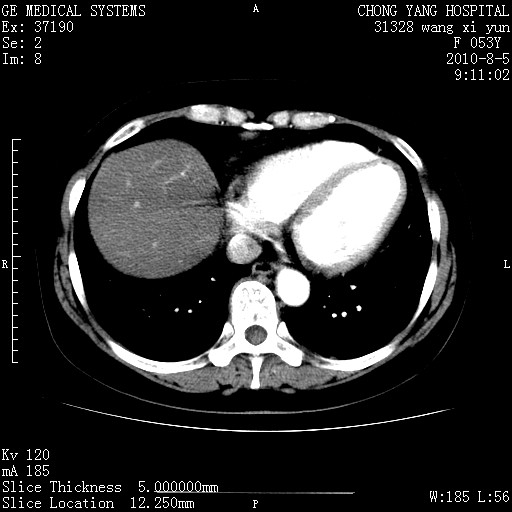

标题: CT28214:F41Y 血尿二十天,建议盆腔平扫加增强。

1)考虑肝左叶胆管细胞癌。2)脂肪肝。